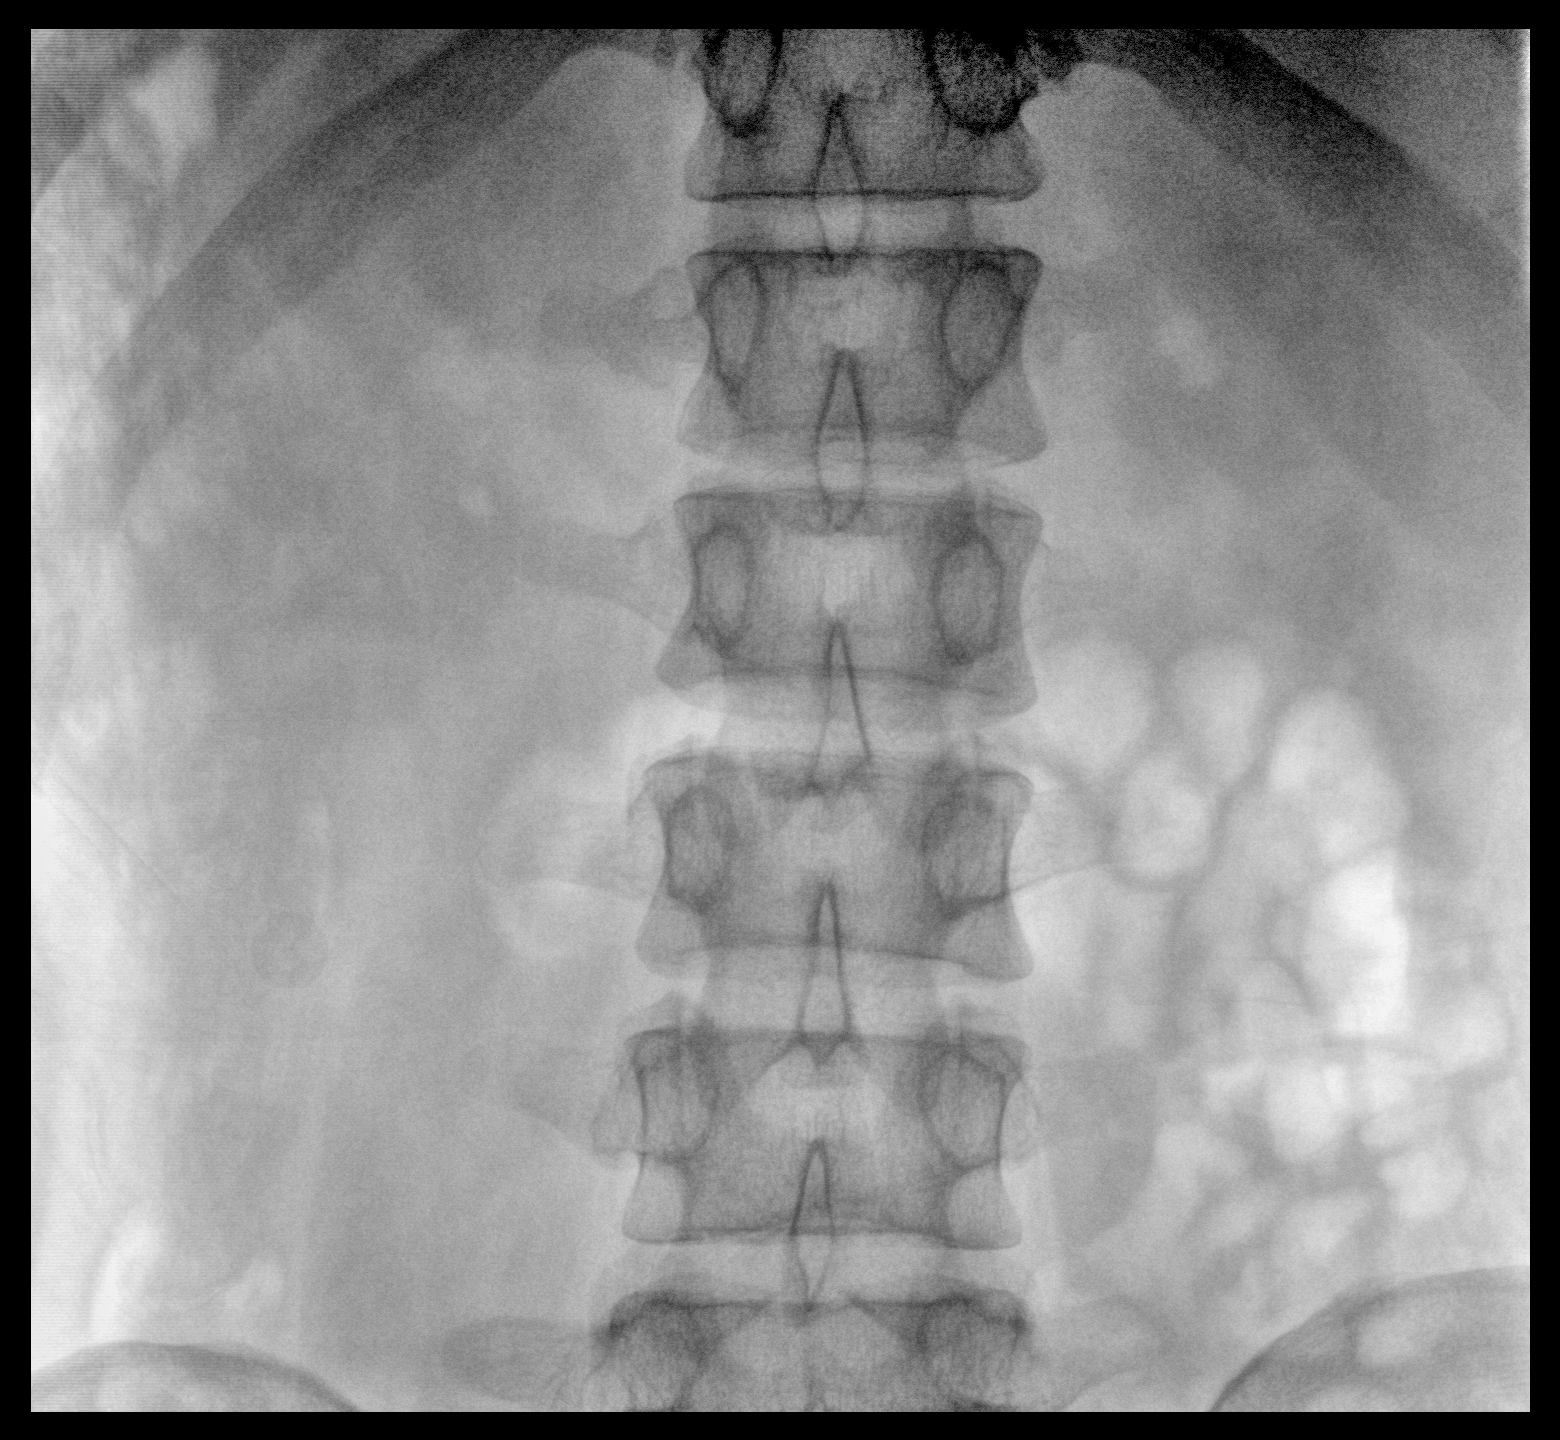

大尺寸動態平板探測器,高DQE、低噪聲、圖像清晰。采用多分辨率圖像增強處理技術,不同部位不同圖像處理算法,滿足客戶多樣化的需求。

采用智能變頻脈沖透視技術,優化圖像質量的同時降低輻射劑量,呵護醫患健康